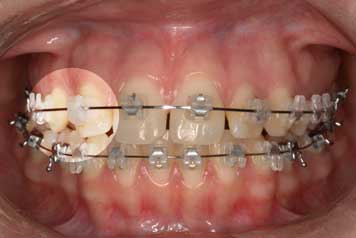

Etapa 1

Tratamiento con ortodoncista, que busca generar el espacio necesario para la correcta ubicación de la pieza ausente.

Implante por Agenesia Dentaria Implante por Agenesia Dentaria